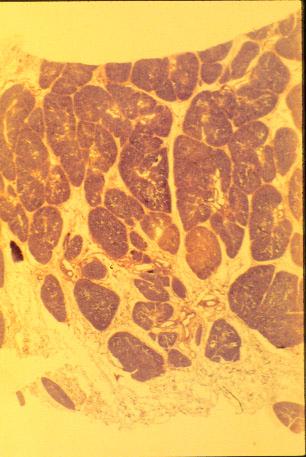

K-slide 55: Note the many lobules which make up this gland.